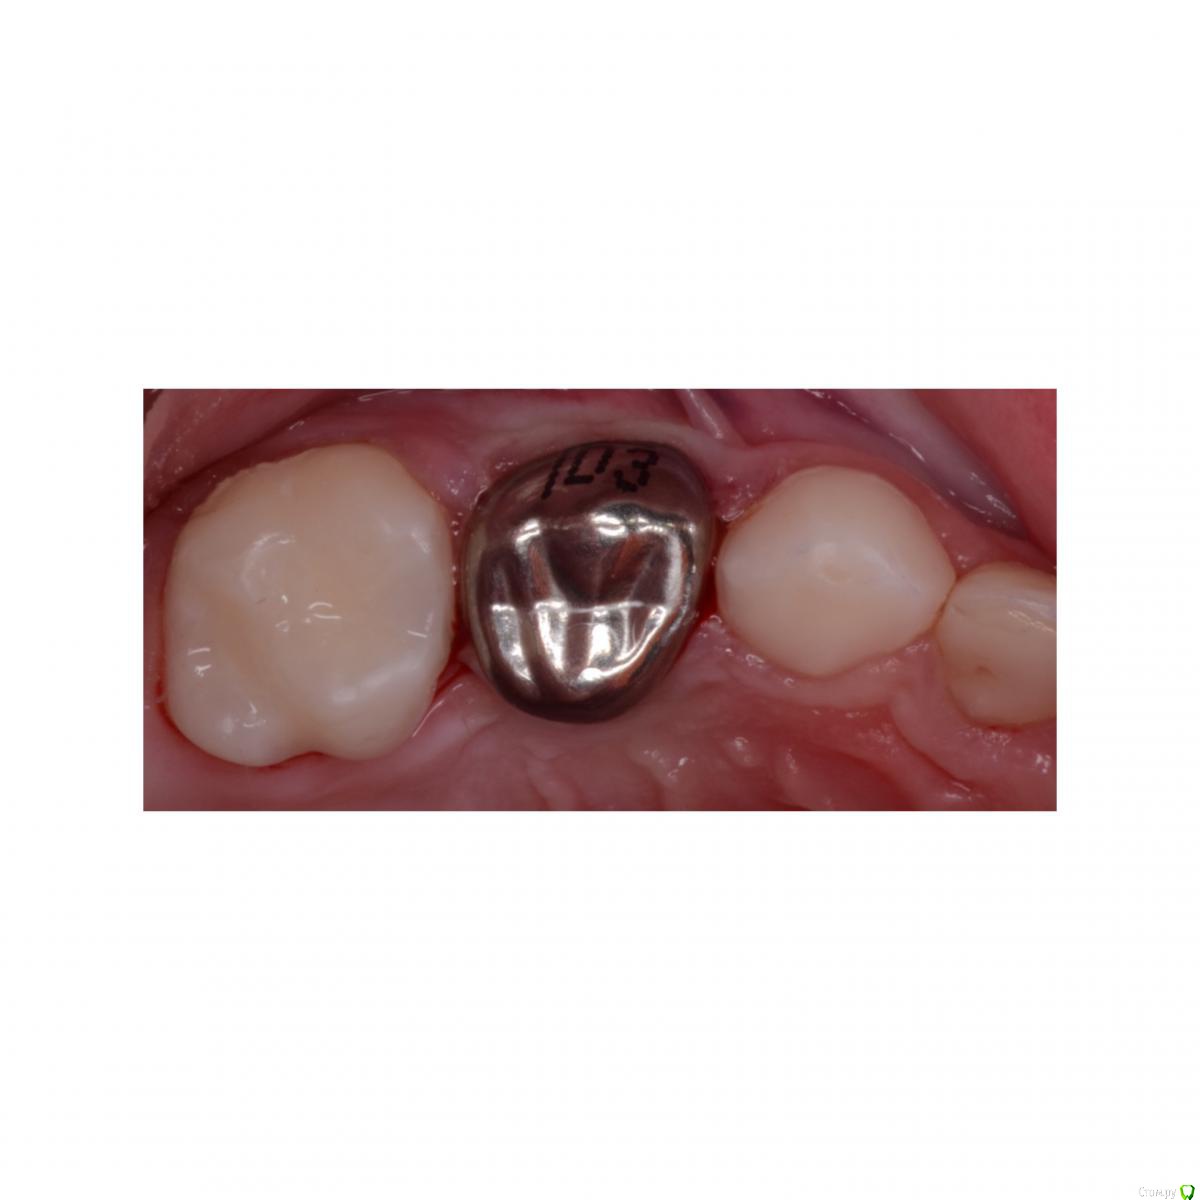

CRAZYDUCK Опубликовано 11 февраля, 2020 Автор Поделиться Опубликовано 11 февраля, 2020 Физиологическая смена зуба , восстановленного ранее стандартной коронкойtrim.EAB9F42F-C9D4-43B2-B836-171869F3A129.MOV 4 Ссылка на комментарий

CRAZYDUCK Опубликовано 11 февраля, 2020 Автор Поделиться Опубликовано 11 февраля, 2020 Случай перелечивания через год после лечения в наркозе . Появился кариес на контактных поверхностях . Лечили в ЗакС . Это лечение одного сегмента . Всего пролечила 4 сегмента в ЗакС .девочке 4 годика . На момент последнего лечения очень устала ,на контакт шла с трудом . Но смогли договориться . В наркозе я не лечу , только в ЗакС . В наркоз отправляю к врачам , в навыках и знаниях которых уверена .Лечили кариес клыка и пятого , четвёртый был в наркозе нарощен со всех сторон , поэтому - коронка . 2 Ссылка на комментарий

CRAZYDUCK Опубликовано 21 февраля, 2020 Автор Поделиться Опубликовано 21 февраля, 2020 Почему-то не по порядку фото грузятся . Ребёнок 4 года , ранее был опыт лечения в наркозе , 7.5 восстановлен окклюзионно и вестибулярно , 7.4 окклюзионно . На фото «до» видно налёт в пришеечной зоне . Восстановила коронками в ЗакС 1 Ссылка на комментарий